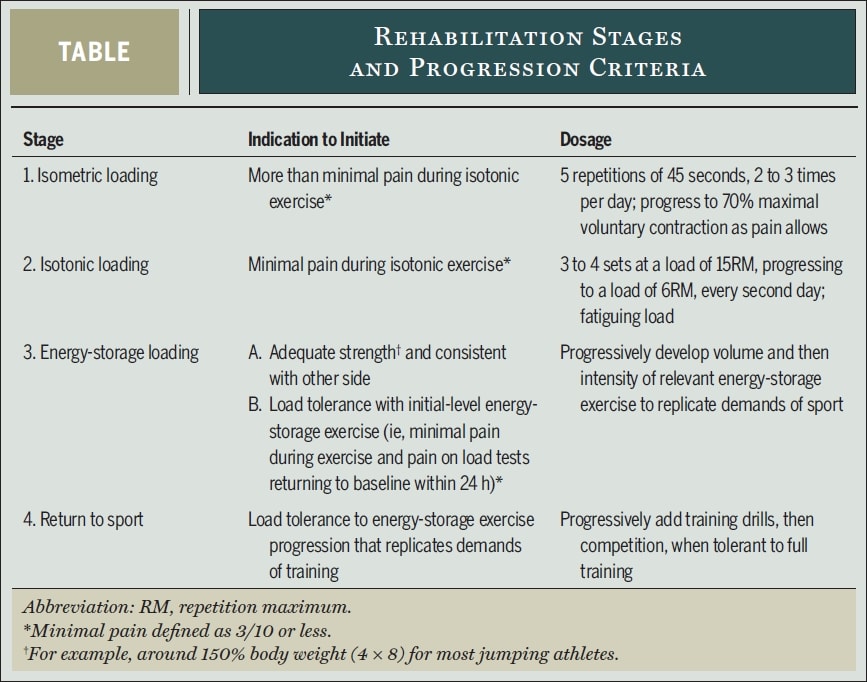

那么,这样的重慢阻力项目是怎样的呢? 腱鞘炎顶级研究人员彼得-马利亚拉斯(Peter Malliaras)、吉尔-库克(Jill Cook)、克雷格-珀达姆(Craig Purdam)和埃博妮-里奥(Ebonie Rio)在他们的论文(2015 )中提出了以下基于证据的 4 阶段康复方案:

让我们仔细看看每个康复阶段:

第 1 阶段--减轻疼痛: 等距加载

- 每天 2-3 次,每次 5 次,每次 45 秒,进行等长中距离(膝关节屈曲 30-60°)单腿股四头肌运动,运动量为中等运动量的 70%。

- 应在可承受的范围内尽快增加阻力。

第 2 阶段--恢复肌肉体积和力量,诱导肌腱适应: 等张负荷

- 当四肢可以等速负重,且疼痛感不超过 NRS 3/10 时,就可以开始这一阶段。

- 最初在膝关节屈曲 10 至 60°之间进行重度、缓慢的阻力活动,在疼痛允许的情况下,逐渐增加至屈曲 90°以上。 其中包括压腿、深蹲、黑客深蹲、劈叉深蹲和坐姿膝关节伸展。 开始时双腿站立,疼痛允许时再逐渐改为单腿站立。 Kongsgaard等人每隔一天以相当于15RM的阻力进行3至4组训练,然后逐渐增加到6RM。 在进行大运动量慢阻力练习的间隙,继续第一阶段的练习。

第 3 阶段--储能加载: 提高负载耐受性,改善功率

- 当运动员达到良好的力量水平,并能承受约为体重 150% 的单腿负荷时(例如,4 组 8 次的单腿推举),如果在训练后 24 小时内没有出现 NRS 3/10 以上的疼痛,就可以开始这一阶段的训练。

- 起始动作可以是双腿压腿,负重为体重的 3 倍(或单腿为 1.5 倍),因为这会产生与垂直起跳落地时相同的髌骨力。

- 带停地、起跳和着地、加速和减速、切入和变向的跳跃序列

- 量(跳跃次数、接触次数)先于强度(高度、速度)进步

- 每隔三天进行一次,并在第二天和第三天继续进行等长负荷和等张负荷。

第 4 阶段--重返运动场

- 分级恢复训练和比赛,最初的训练量和强度与第 3 阶段的训练量和强度相匹配,然后再根据具体运动情况的需要增加训练量和强度。

- 保持每周至少两次的第二阶段练习,并最终在训练前或训练后进行第一阶段练习。